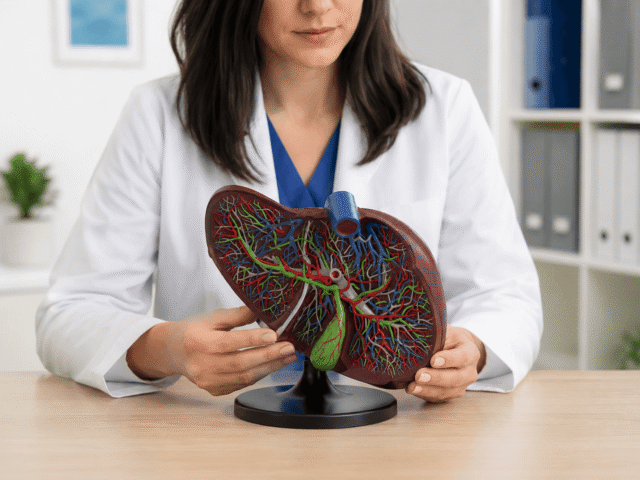

Pročitajte višeMasna jetra (nealkoholna steatoza) – Tiha epidemija modernog doba

Jetra je najsloženiji organ u ljudskom telu. Ujedno i organ sa važnim funkcijama. Njena glavna uloga je prečišćavanje krvi od...